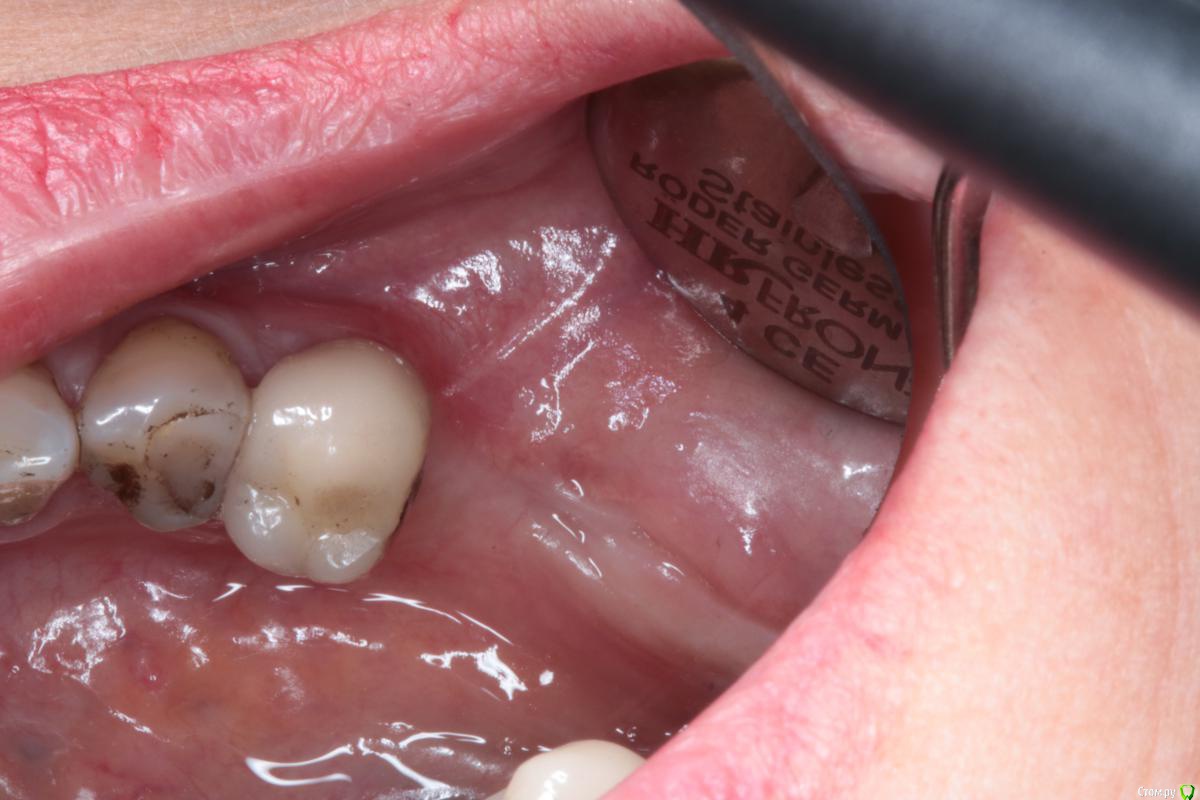

igorgergg Опубликовано 17 июня, 2018 Поделиться Опубликовано 17 июня, 2018 Всем привет, пациентке было сделано нкр в области 36 зуба с необиотековской сеткой. Щечный лоскут плохо натягивался после рассечения надкостницы и тупого прохождения ножницами и язычного отслаивания, пришлось сделать послабляющий между 4 и 5. Но и его не сильно хватило, лоскут язычно натягивался всего на 0.5 см где-то, чувствовал что натяжение есть.Хотя раньше, когда мобилизовался, хватало обычного рассечение надкостницы и язычно отслаиться. В итоге сетка прорезалась, но мне кажется есть и вторая причина почему, так как возможно на сетке были углы острые поэтому и не затянулась. Ушивался 2-3 П- образных и сверху простые узловые наглухо. Фото прилагаю. Сейчас хочу с мембраной эволюшен переделать, но есть опасения что причина также и в натяжении после ушивания, так как даже с послабляющим я не смог натянуть без натяжения лоскут. Также сейчас слизистая в этом месте подвижная и тонкая стала, что может усложнить операцию и ушивание. Чтобы был успех исключаю титановую сетку и вопрос в ушивании и также вопрос может пластику десны первым этапом сделать в такой ситуации (смещенным лоскутом с трансплантатом?), так как на этом месте сейчас щека натянута, на фото видно. Дайте плз обратную связь) Опыт есть, но его не так много Ссылка на комментарий

igorgergg Опубликовано 22 июня, 2018 Автор Поделиться Опубликовано 22 июня, 2018 Что за Pt на семёрке ?Тут с Эволюшн +2мм кости вестибулярного получить достаточно. Зачем сетки ?Имплант сразу.семерку удалили уже смущает тонкий биотип, думаю что сложно будет ушиться. в области пятеркки также прикрепенки не стало после нкр Ссылка на комментарий